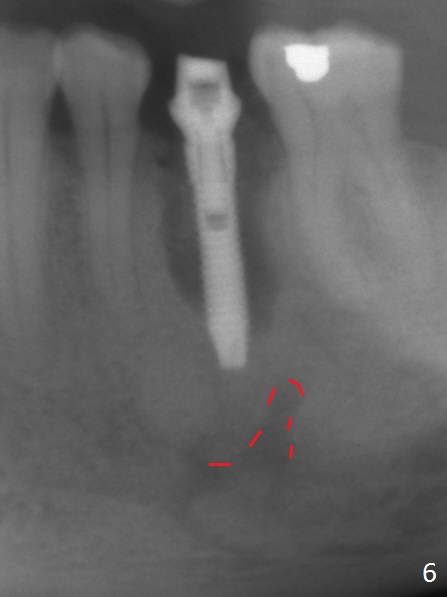

Extraction of the lower left 2nd premolar with vertical fracture (Fig.1,2 >) is easy because of peri-radicular radiolucency. The apical end of the osteotomy is not shown with a 2 mm pilot drill (Fig.3) or a 3.8x18 mm implant (Fig.4) in place. It appears that the implant is not placed deep enough. Following 3-4 more turns of the implant and placement of a 5.5x4(3) mm abutment (Fig.5 A), allograft is placed (*). A postop panoramic X-ray is taken (Fig.6); the osteotomy could have been deepened to reduce the possibility of periimplantitis. Retrospectively, the panoramic X-ray should be taken after use of the pilot drill. The bone around the implant appears to have regenerated 4 months postop (Fig.7,8). Bone density appears to continue increasing 9 months postop (i.e., 4.5 months post cementation, Fig.9). Bone loss is minimal 2 years post cementation (Fig.10).